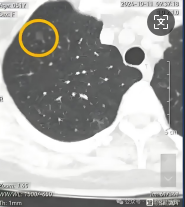

三、肺部磨玻璃结节真正长大

这种情况发生率不高,很多短期内快速增大的结节,反而更高概率是炎症性病变,真正是肿瘤性病变的磨玻璃结节,一般不会短期内内快速增大。

当然,我们举例针对的是邻近手术切除边界的肿瘤,平时遇到的误差导致的原因,遇到具体情况还需到专科进一步检查诊治。不可盲目对比。